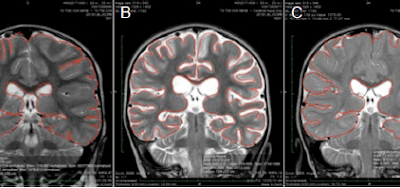

Dr. Gunnar Heuser, a toxicexposure specialist, documentedresults of a series of hyperbarictreatments on 9 patients sufferingfrom Impaired Brain Function. Thepurpose was to study the effects of1.3 ATA of hyperbaric therapy onthose patients. His patientsincluded...